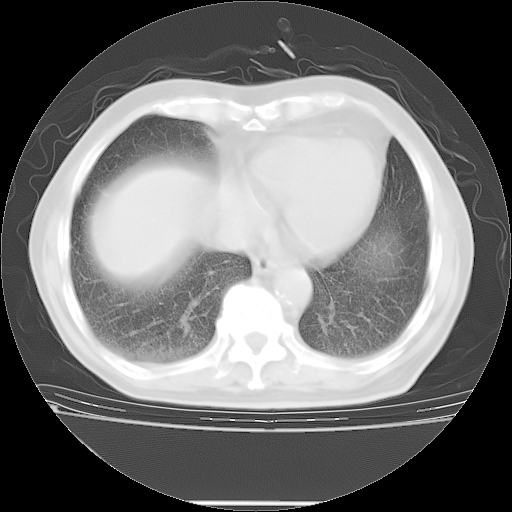

今天复查肺部CT,发现双肺广泛磨玻璃样改变。所以我把3月19日和5月9日相隔50天的肺部CT上传。请大家会诊。

2009年3月19日肺部CT片。

2009年3月19日肺部CT